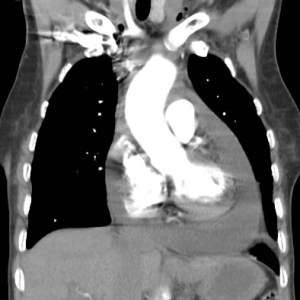

En el corte de TC con contraste vemos la sonda desplazada a la derecha de la línea media (flecha azul), un hematoma mediastínico (flecha verde) provocado por la rotura aórtica (flecha naranja), y un hemotórax izquierdo (flecha amarilla).